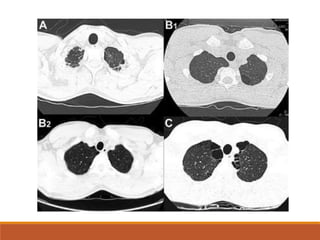

DIAGNÓSTICO

TC de tórax  en casos de NEP pequeños o loculados.